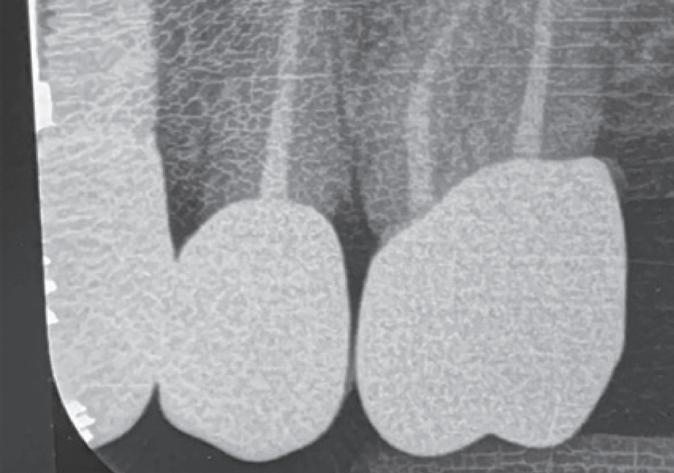

The standardisation of treatment procedures has resulted in less emphasis on craftmanship. I have quite a few gold restorations in my own mouth, two of which were placed there by a very fine dentist in 1968, both are still intact with no breakdown around the margins and both the teeth are functioning well, despite one of them having been root treated with silver points at the time. I take regular radiographs and there are absolutely no problems. I placed a number of gold restorations in my wife’s mouth before we were married in 1973 and they, too, are all still functioning well. And yet my laboratory, which

employs more than 30 technicians, has only one person who is still capable of producing good metal margins and despite all the emphasis on digital restorations and aesthetics, the dentists that I treat as patients prefer gold in their own mouths and for their families wherever possible.

In 1975, one of my patients who was 18 years old became involved in a car accident; he hit the steering wheel with his chin and sustained 2 horizontal fractures in his 31, both quite a way subgingivally. The 41 and 32 were intact. The normal treatment at that time would have required extraction of the 31 and the placement of a partial denture or a bridge to replace the missing tooth.

Knowing that he had nothing to lose, he agreed to let me experiment on him. I extirpated the 31, drilled 10mm past the apex using a sterile Kurer Post spiral drill that matched the diameter of my titanium wire. I sterilised the Titanium using a

dry heat furnace, cut it to length less some 5 mm, coated it in endodontic sealer 10 mm short of the end to make sure that I didn’t extrude sealer past the apex, tapped it into place using my implant hammer and a Unitek pin placement tool and then using G.P. points, I sealed the tapering part of the root canal. I placed an amalgam seal on the lingual. The tooth became discoloured, the patient got married and moved to Queensland. I lost contact with him in the late 70s.

Fifteen years ago, I had to refer an elderly patient to an Oral Surgeon to have some teeth removed. We got a phone call at the surgery from her daughter who wanted to understand what was happening. I called back what was a Queensland number and identified myself to the man who answered the phone. On hearing my name, he identified himself and asked whether I remembered him. Of course I did. I asked him whatever happened to that tooth. He said that it didn’t cause any problems but that it had turned jet black and he and his wife got sick of looking at it. He’d had it extracted some 5 years earlier and it was replaced by a conventional implant. I asked him about the teeth either side of it and he said that they were still there and perfectly OK.